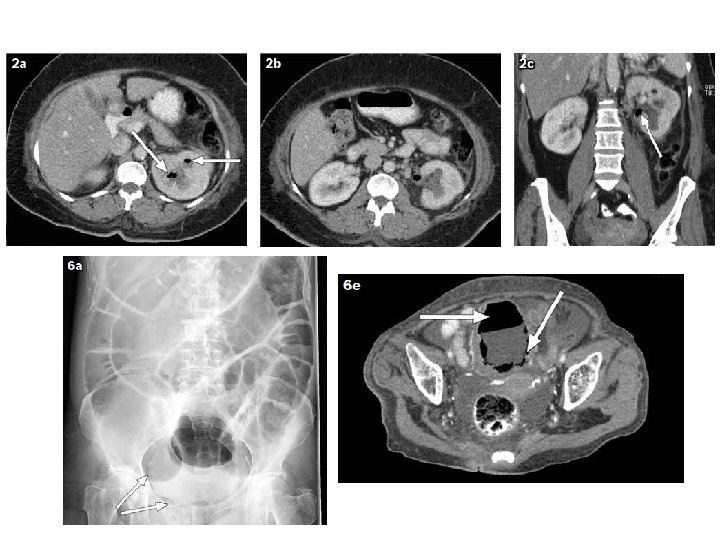

Prognostic classification • Two classification system , based upon CT scan finding • Type I : Renal parenchymal necrosis with absence of fluid collection or presence of streaky or mottled gas pattern Type II : Renal or perirenal fluid accompanied by bubbly gas pattern or gas in the collecting system Radiology 1996, 198, 433 -438. Type I EPN is associated with worse prognosis Mortality rate Type I 69 % VS Type II 18 %

Prognostic classification Class 1: Gas in the collecting system only Class 2: Gas in the renal parenchyma without extension to the extrarenal space Class 3 A: Extension of gas or abscess to the perinephric space, between the fibrous renal capsule and the renal fascia Class 3 B: Extension of gas or abscess to the pararenal space, space beyond the renal fascia and/or extension to adjacent tissue Class 4: Bilateral emphysematous pyelonephritis or solitary functioning kidney with emphysematous pyelonephritis Arch Intern Med 2000 Mar 27; 160(6): 797 -805.

Arch Intern Med 2000 Mar 27; 160(6): 797 -805.